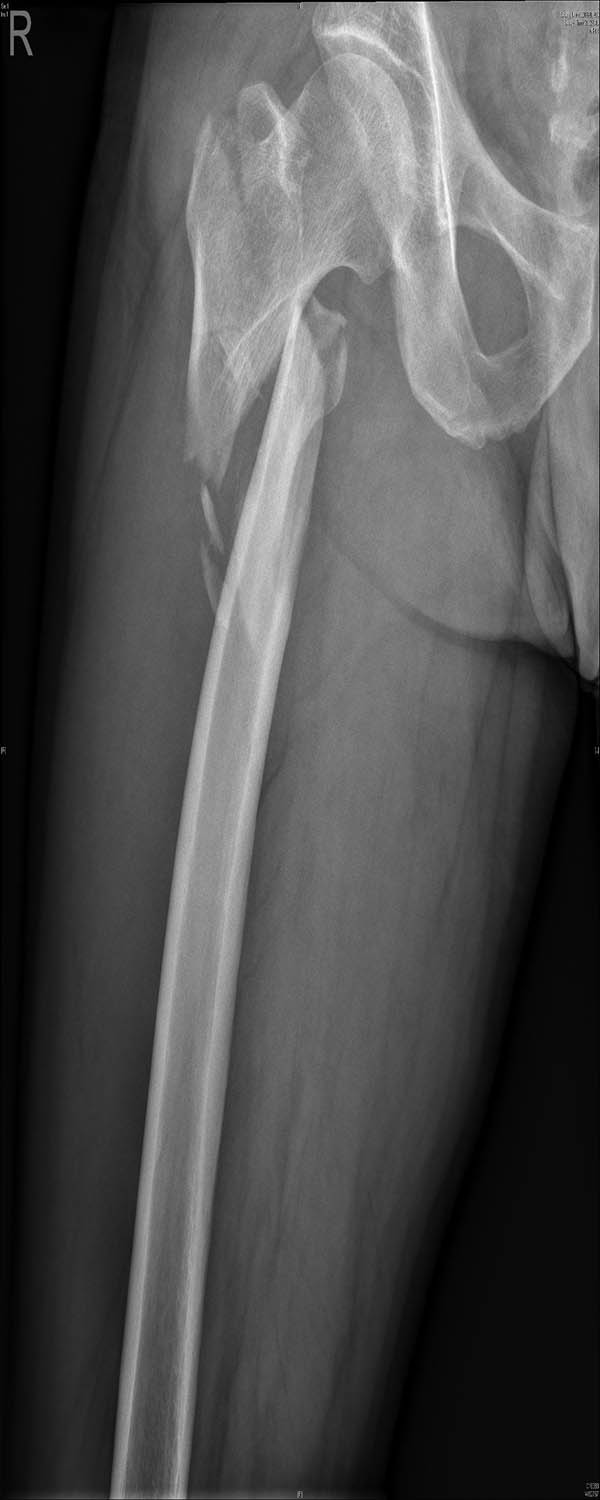

External fixation via the AIIS and distal femur was performed by a single surgeon under general anesthesia without regional nerve blockade during emergency surgery. External fixators derived from AO (Synthes, Ltd., Paoli, PA), Trauson (Trauson, Ltd., Changzhou), and Carefix (Carefix, Ltd., Shanghai) were used. Patients were placed in a supine position on the operating table. A C-arm was used to locate the points of the AIIS, and a minimal incision of 1–2 cm in length was made. The deep fascia of the pelvis and femur were incised. Proximally, the lateral femoral cutaneous nerve was protected by a surgical hook. One pin (diameter 6.0 mm, length 180 mm, thread length 60 mm) was placed at the AIIS on the same side as the PFF. Distally, two crossing pins (diameter 6.0 mm, length 180 mm, thread length 60 mm) were placed at the distal femur through two minimal incisions. High-strength and fully transparent carbon fiber rods (diameter 8 mm, length 400 mm) were fixed, manipulative reduction was performed along the strength line under the C-arm, and the clamps were tightened. The incisions were then sutured. A typical case is presented in Figures 2–5.

A 42-year-old man fell from height and his X-ray examination revealed that a femoral intertrochanteric fracture had occurred and that the fracture was displaced.